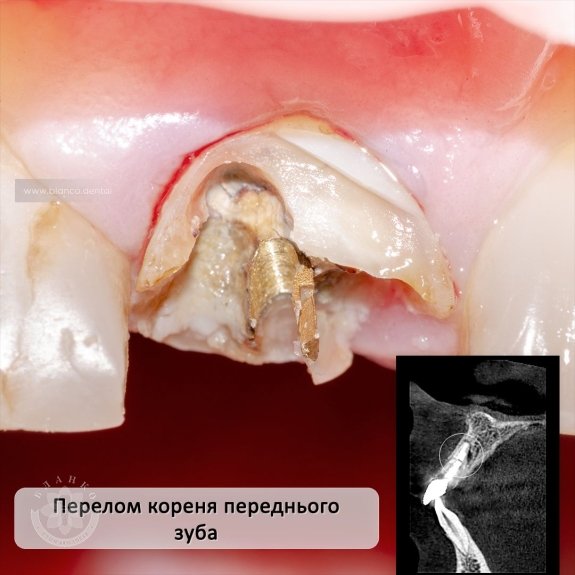

На комп’ютерній томограмі визначається фрактура (перелом) кореня зуба. Такі зуби відновленню не підлягають.